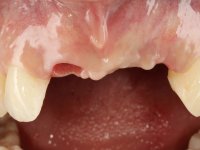

Female patient, 30 years old, non-smoker. The patient appeared in consultation after orthodontic treatment and placement of an implant at tooth site 2.1. Teeth 3.7, 3.6 and 4.7 had root canal therapy and teeth 1.5, 2.5, 2.6 and 4.5 had undergone extensive restorations. Patient had a thin periodontium and showed a satisfactory oral hygiene. After surgical exposure of the implant, it proved to be positioned improperly. Prosthetic rehabilitation of the implant proved impossible by adopting acceptable aesthetic criteria. The patient carried an acrylic temporary crown on a stump screwed as a fallback solution for six years, as she had not accepted the offer to remove the implant. After this time, patient returned to consultation with an abscess in tooth 1.1. After analyzing the situation, it was verified that teeth 1.1 and 2.2 had indicated extraction and the implant should be removed or submerged.

In the initial phase, it was proposed to the patient to perform the surgical implant exposure and after clinical evaluation, make prosthetic decisions. Once the healing screw was placed and the soft tissues were healed, an inadequate position of the implant was found. In view of the dramatic situation, the patient was proposed to remove the implant and put a new one after tissue regeneration. This proposal was rejected by the patient, who suggested temporary rehabilitation of the current implant. A new proposal was then made, to rehabilitate the implant, consisting of a screwed abutment, and on this, the placement of an acrylic crown with coronal and gingival components. After 6 years with the provisional treatment, the patient appeared in consultation with an abscess in tooth 1.1. After clinical and imaging analysis, it was decided to remove teeth 1.1 and 2.2, submerge the implant, place two implants at the site of 1.1 and 2.2 and perform adequate tissue regeneration. Temporization would be done with a provisional 3-element bridge, adhered with a net to the neighboring teeth. After osseointegration, definitive rehabilitation would be done with a 3-element bridge, including zirconia infrastructure and ceramic cover.

The surgical implant exposure and the healing screw placement proved to be a negative surprise regarding its position. Since the proposed removal of the implant was refused, we advanced to its provisional rehabilitation. An open tray impression technique was done, and a screwed abutment with a coronal and gingival component and an acrylic crown were made in the laboratory, using these two components. The provisional crown was placed in the mouth until a final decision was made. Six years passed before the patient returned to the clinic with an abscess on tooth 1.1. The choice to remove teeth 1.1 and 2.2 was made, to create a provisional 3-element bridge with a net to be adhered to the adjacent teeth. Surgery was planned and performed, placing the two implants at the site of 1.1 and 2.2, and the implant at the 2.1 site was cut with the objective of submerging it, while adequate tissue regeneration was performed (Surgical Work performed By Dr. Manuel Neves). During osseointegration, the patient used the fixed provisional bridge. A first impression was made for confection of a zirconia screwed provisional bridge, which worked the soft tissues for twelve weeks. The definitive impression was made with the individualisation of custom impression copings. Final rehabilitation was done with ceramized abutments, and also a bridge with zirconia infrastructure and ceramic cover. Due to the inclination of the implant placed at the site of tooth 1.1, the bridge required cemented fixation.